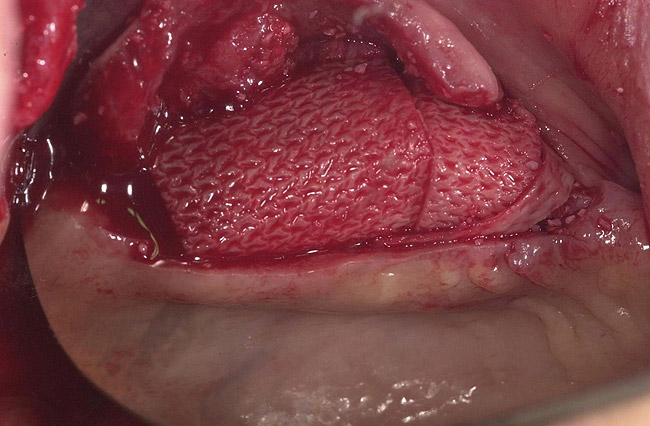

Figure 13  Ridge-split osteotomy with lateral wall expansion.

Figure 13